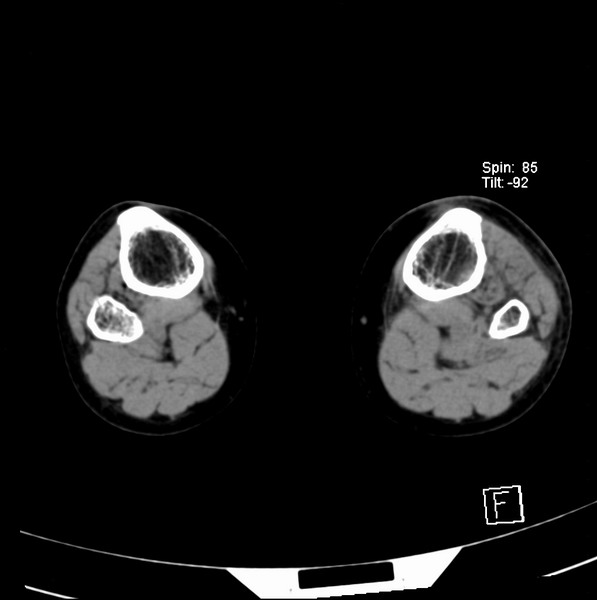

标题: CT21917:右腓骨小头是否骨软骨瘤? [打印本页]

标题: CT21917:右腓骨小头是否骨软骨瘤?

女、43.

不是骨软骨瘤,“牵拽征”,正常变异。有平片吗?

正常变异,“牵拽征”,比目鱼肌牵拽.